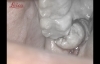

しばらくして、歯茎へメスを入れていきます

親知らずを取り出しやすい様に歯茎を切開して露出させます

これだけ切られたのに麻酔のおかげか、全く痛みはありません!

カッターで親知らずを分割していきます

分割された親知らず

松木先生と助手さん付きっきりで抜歯は行われて行きます

分割された親知らずの上断面は取り出し成功!

更に下断面も取り出して見事なまでの大穴が開きました

最後に縫合して終了です!